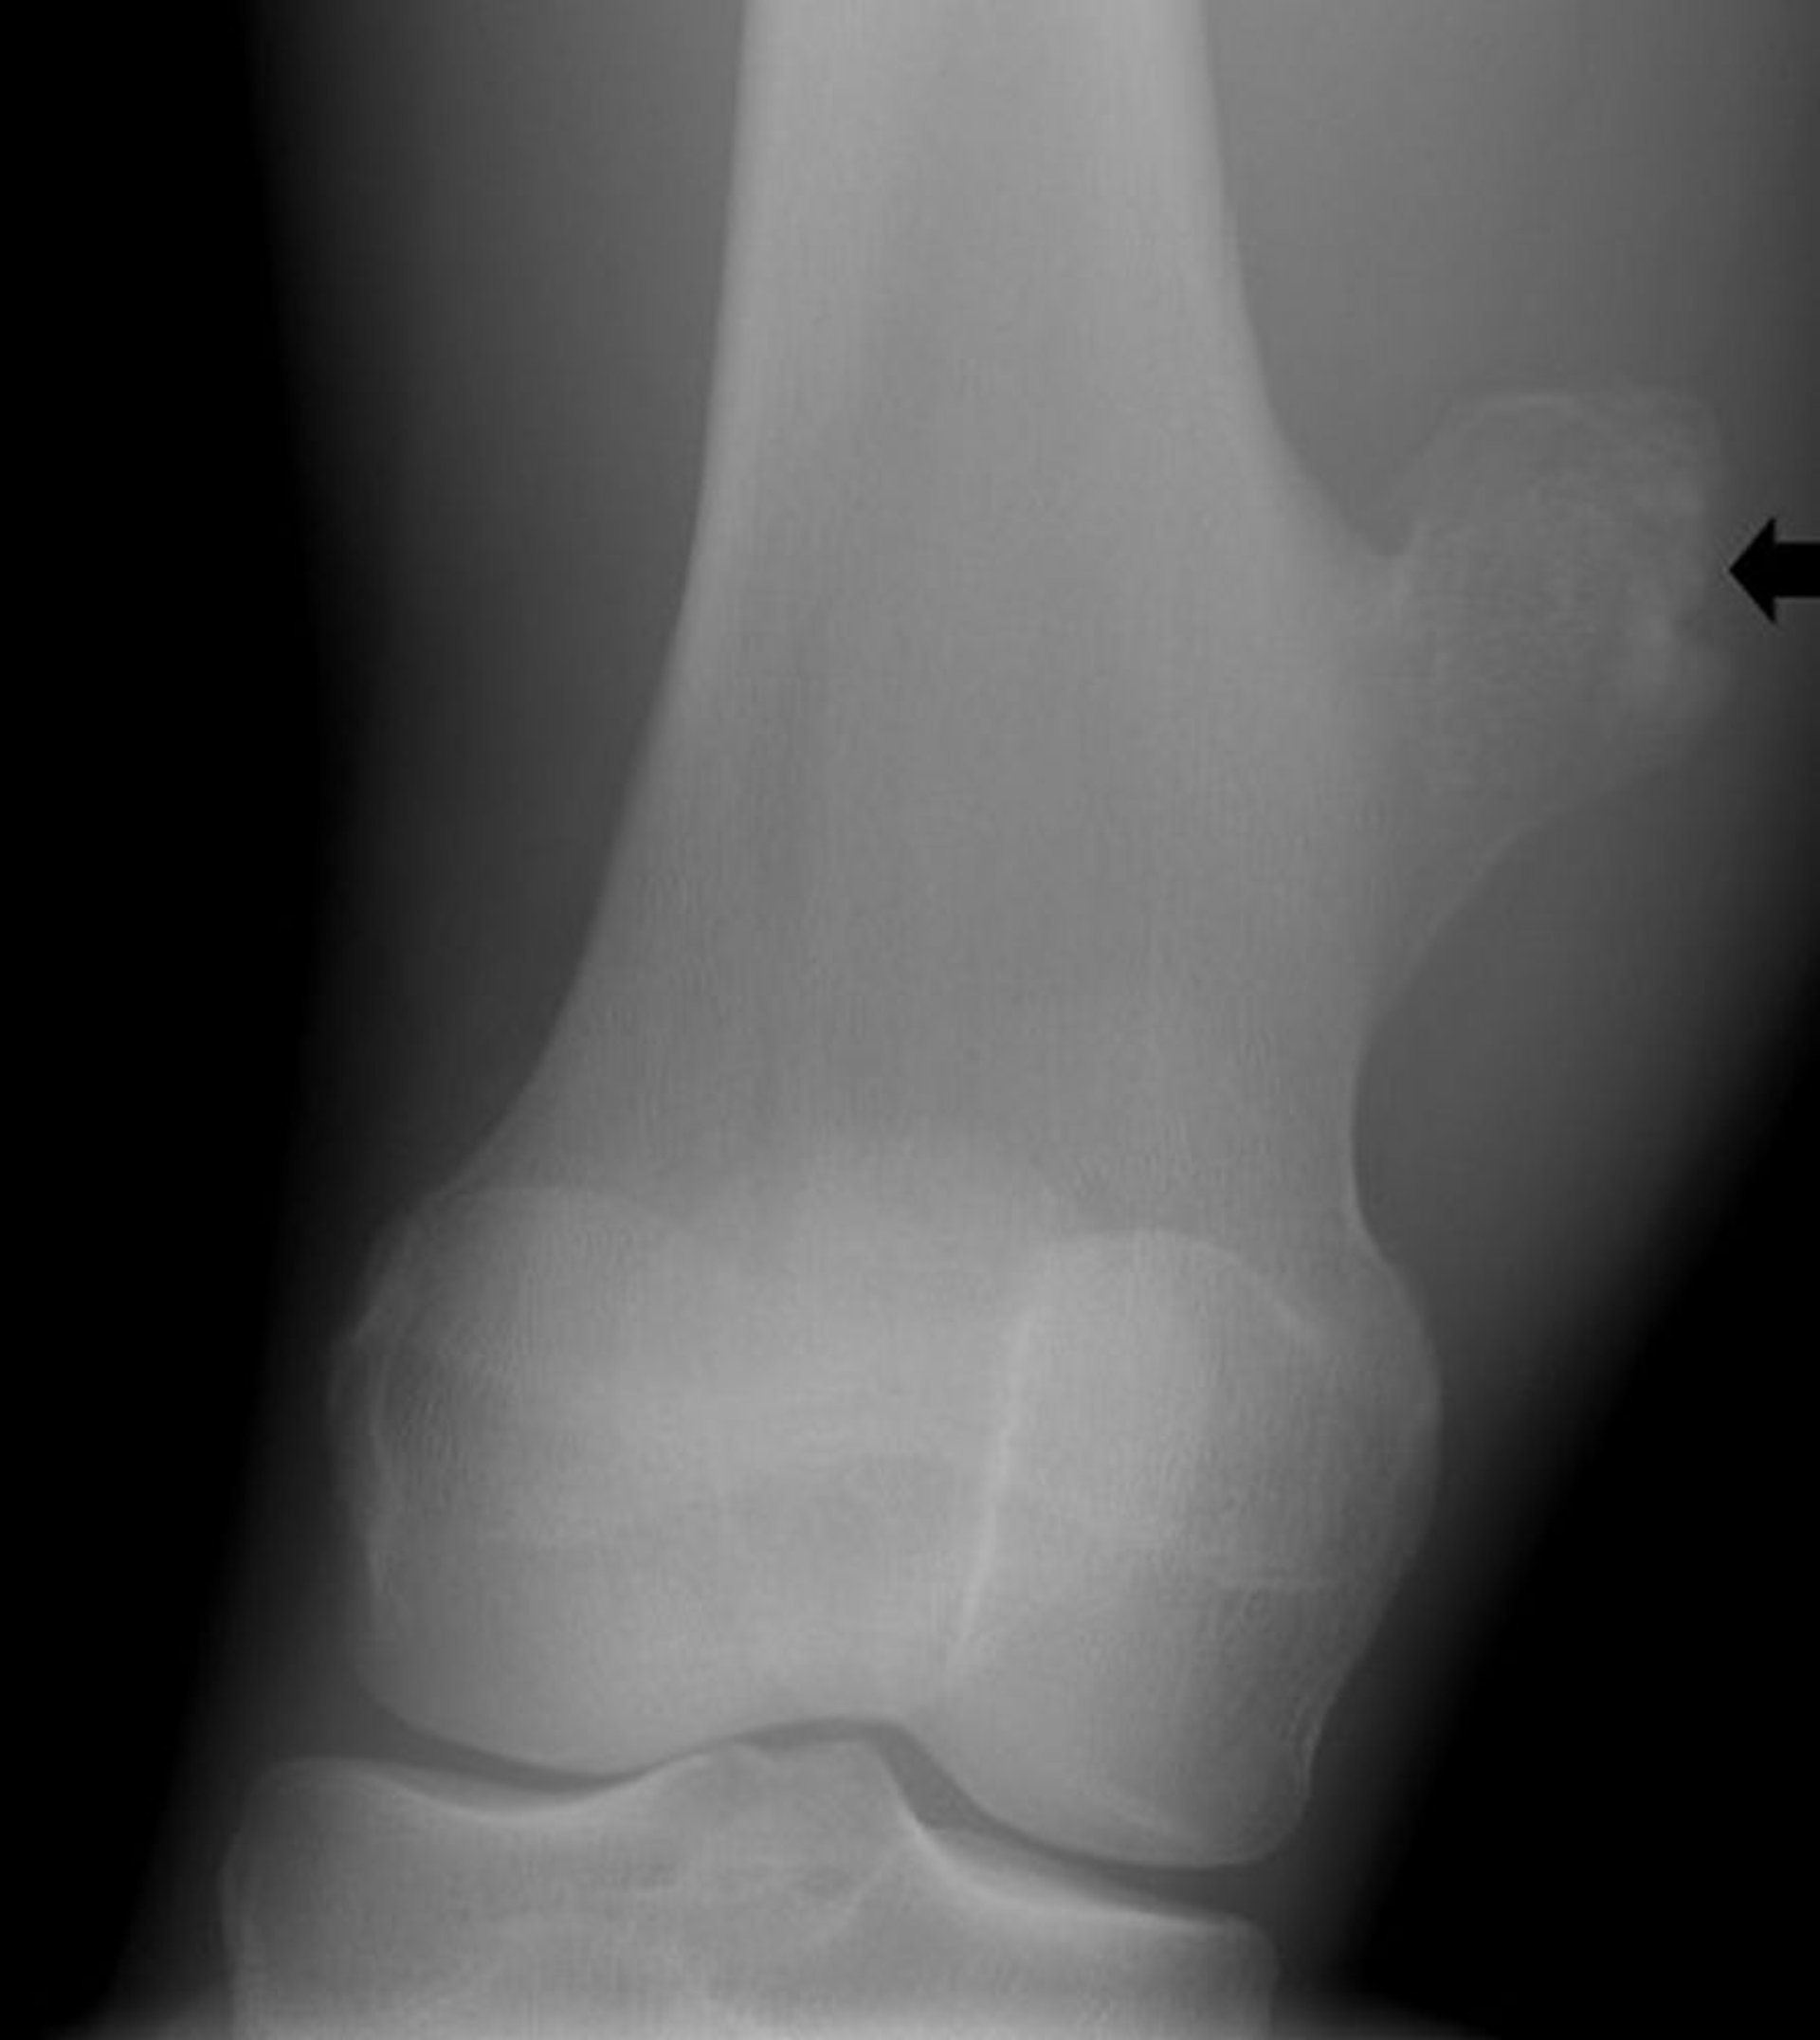

This radiograph of the knee shows a bony outgrowth (arrow) from the femur above the knee joint that is consistent with an osteochondroma.

Image courtesy of Michael J. Joyce, MD, and Hakan Ilaslan, MD.